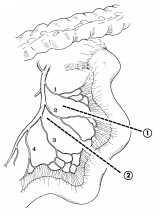

器械吻合器を用いた、咽頭部食道癌摘出後再建法

首の解剖の本と首っ引きで描きました。